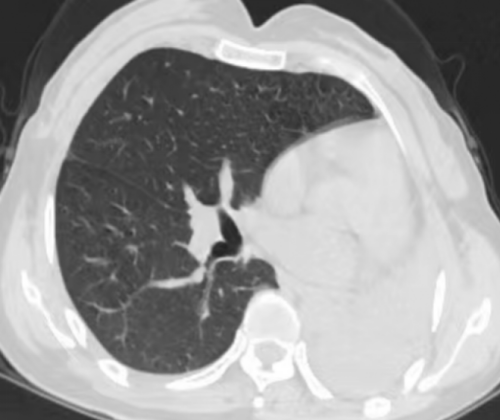

吴丽胸部CT显示左肺“消失”

“为了找回‘消失’的肺,我们给她安排了胸部增强CT。发现其左主支气管狭窄、远端及各叶段支气管闭塞并左肺团片影及肺不张。”据香港马会app

呼吸内镜诊疗部副主任医生刘超群带领团队进一步完善相关术前检查,通过支气管镜和气道内超声,使用高频电刀分次向下,切开长约2cm瘢痕组织,让大量脓液溢出,再通过球囊扩张,扩大其气管,让左主管腔再通,患者咳嗽出大量脓痰,自感气促明显缓解,复查胸部CT,神奇地发现消失的左肺回来了。

复查胸部CT显示左肺复张